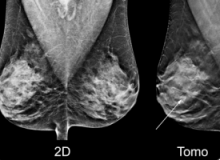

Digital breast tomosynthesis (DBT), also known as 3-D mammography, has come a long way since the first system received U.S. Food and Drug Administration (FDA) clearance in 2011. The modality has seen increased adoption due to the benefit of being able to see through dense fibroglandular breast tissue better than a traditional 2-D mammogram.

February 27, 2019 — Radiologists quickly learn to read 3-D mammography more accurately than they read standard 2-D mammograms, a first-of-its-kind study by a UC Davis researcher has found.